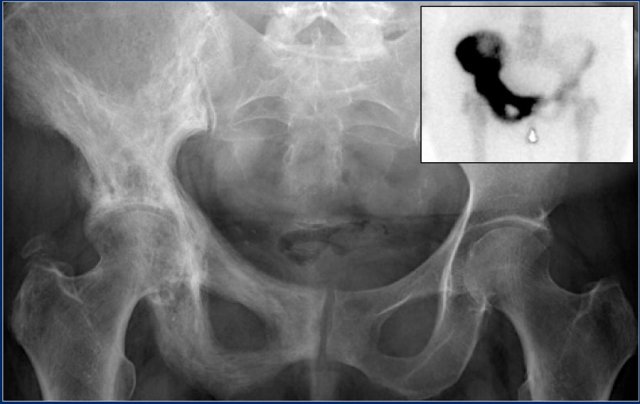

Study the images and then continue reading.

The findings are:

• Pathognomonic triad of bone expansion, cortical thickening and trabecular bone thickening.

• This is the mixed lytic and sclerotic phase of Paget.

• Positive bone scan.

Here we see broadening of the ulna shaft is seen with a mixed lytic-sclerotic appearance and coarse trabeculation.

Differential diagnosis based on the radiograph:

1. Paget's disease

2. Fibrous dysplasia

The intense uptake of the tracer on the bone scintigraphy makes the diagnosis of Paget's disease the most likely.